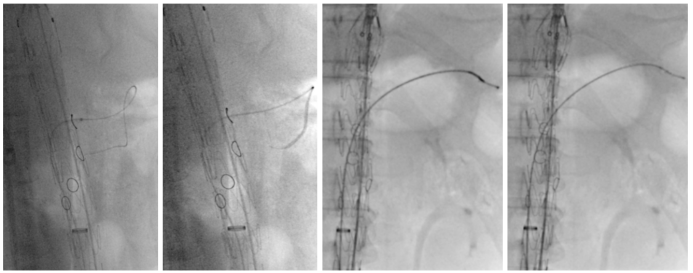

★ 鞘管与导管的“黄金搭档”

Fustar、FusmartTM等可调弯器械的出现使完全经下肢动脉入路修复成为现实。

双大鞘,支架全放开,保持束径,保留后释放。

Fusmart流程:调弯选进;调直跟踪泥鳅导丝至动脉远端;交换硬导丝;退出Fusmart。

Fustar流程:调弯辅助Fusmart选入分支动脉;调直并回退Fustar;导入鞘芯(保持调直状态),循硬导丝到分支动脉,鞘需要超过窗口;